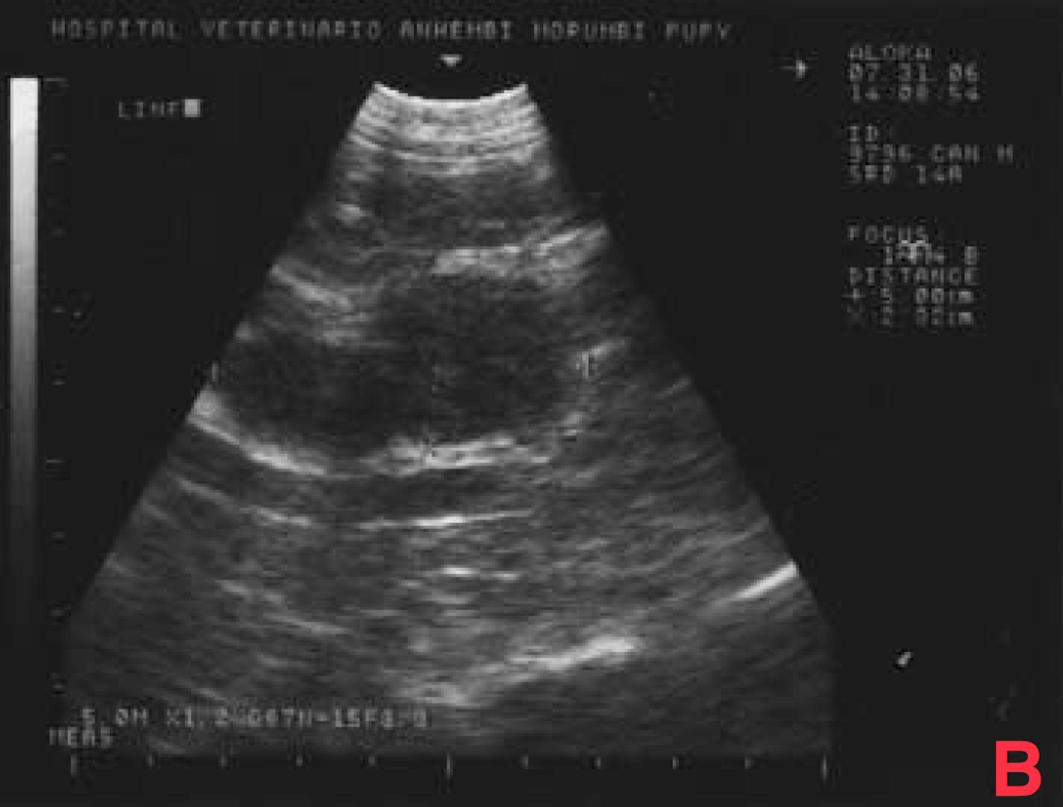

Não houve alterações na avaliação hematológica, na bioquímica (creatinina, ureia) e na radiografia torácica, porém o exame ultrassonográfico mostrou aumento de próstata (4,3 x 3,8 x 2,8cm), com áreas císticas difusas pelo parênquima (imagens sugestivas de hiperplasia prostática benigna/prostatite); somente um testículo em bolsa escrotal; grande aumento de volume em região inguinal esquerda (formação heterogênea em ecotextura e ecogenicidade) e aumento de cadeia de linfonodos sublombares e ilíacos (medindo até 2,4 x 1,6cm, com ecogenicidade e ecotextura heterogêneas) (Figura 3).

Após vinte dias, o estado do animal era bom. Realizou-se então um exame ultrassonográfico de controle, através do qual se observou que o volume da próstata continuava crescendo e que os linfonodos sublombares e ilíacos tinham aumentado, passando a medir 5 x 3,8 x 3,2cm, com ecogenicidade e ecotextura heterogêneas, devendo-se considerar a possibilidade de processo metastático.

O exame ultrassonográfico demonstrou aumento de próstata mais acentuado (6 x 5 x 5,6 cm), com áreas císticas/cavitárias difusas pelo parênquima (sugestivas de hiperplasia prostática benigna/prostatite/neoplasia) e aumento de cadeia de linfonodos sublombares e ilíacos (5 x 4,6 x 4 cm), com ecogenicidade e ecotextura heterogêneas, sugestivo de processo metastático (Figura 9).